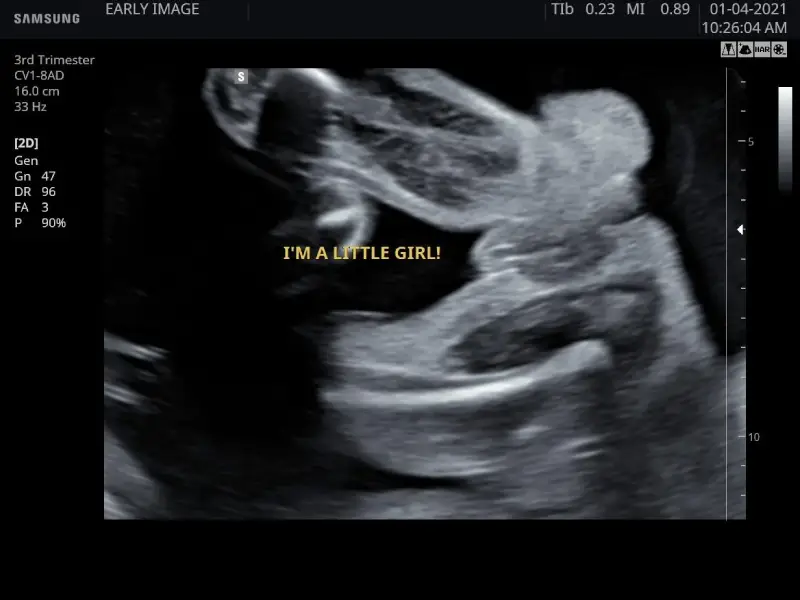

I’m a little girl